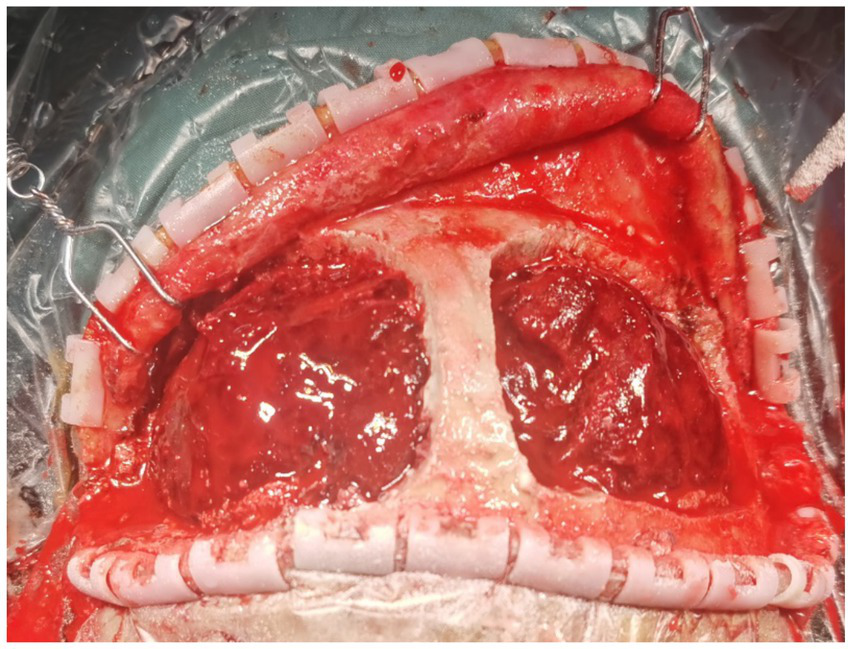

Figure 2

Intraoperatively, after opening the bilateral frontal bone flaps adjacent to the sagittal sinus, a large amount of epidural hematoma is observed.